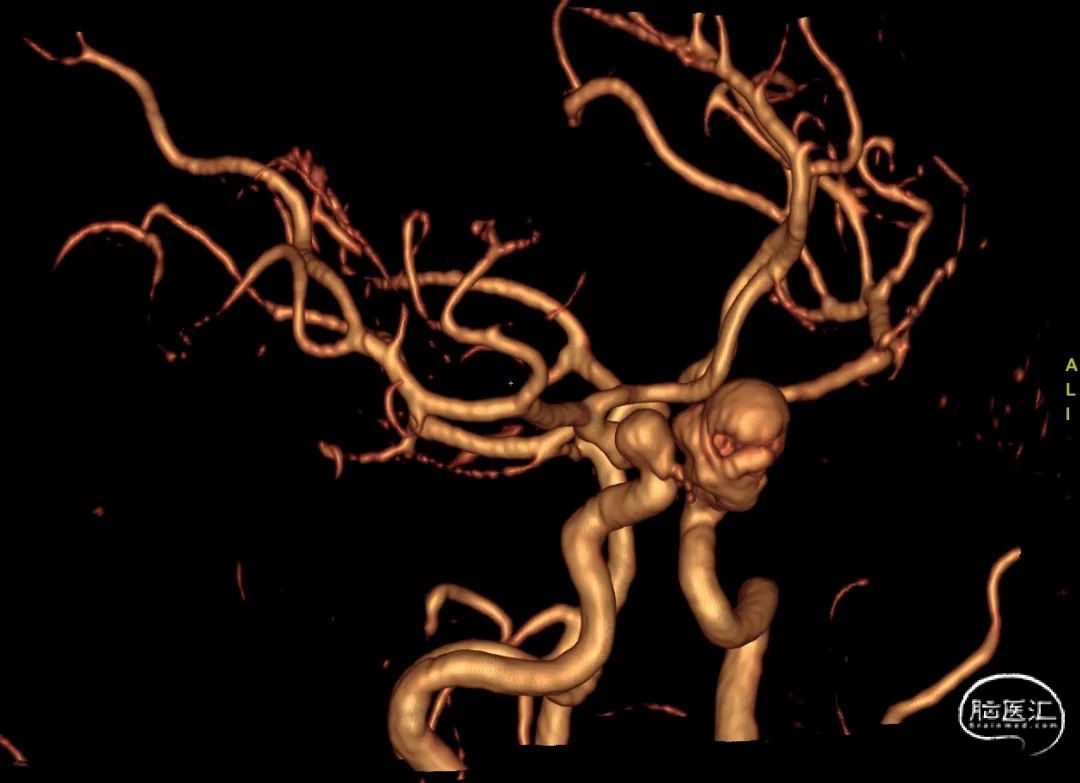

3D-DSA重建结果。